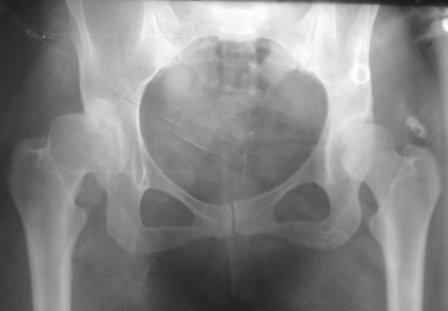

Представляю Р-снимки: обзорная, с отведением и с приведением.